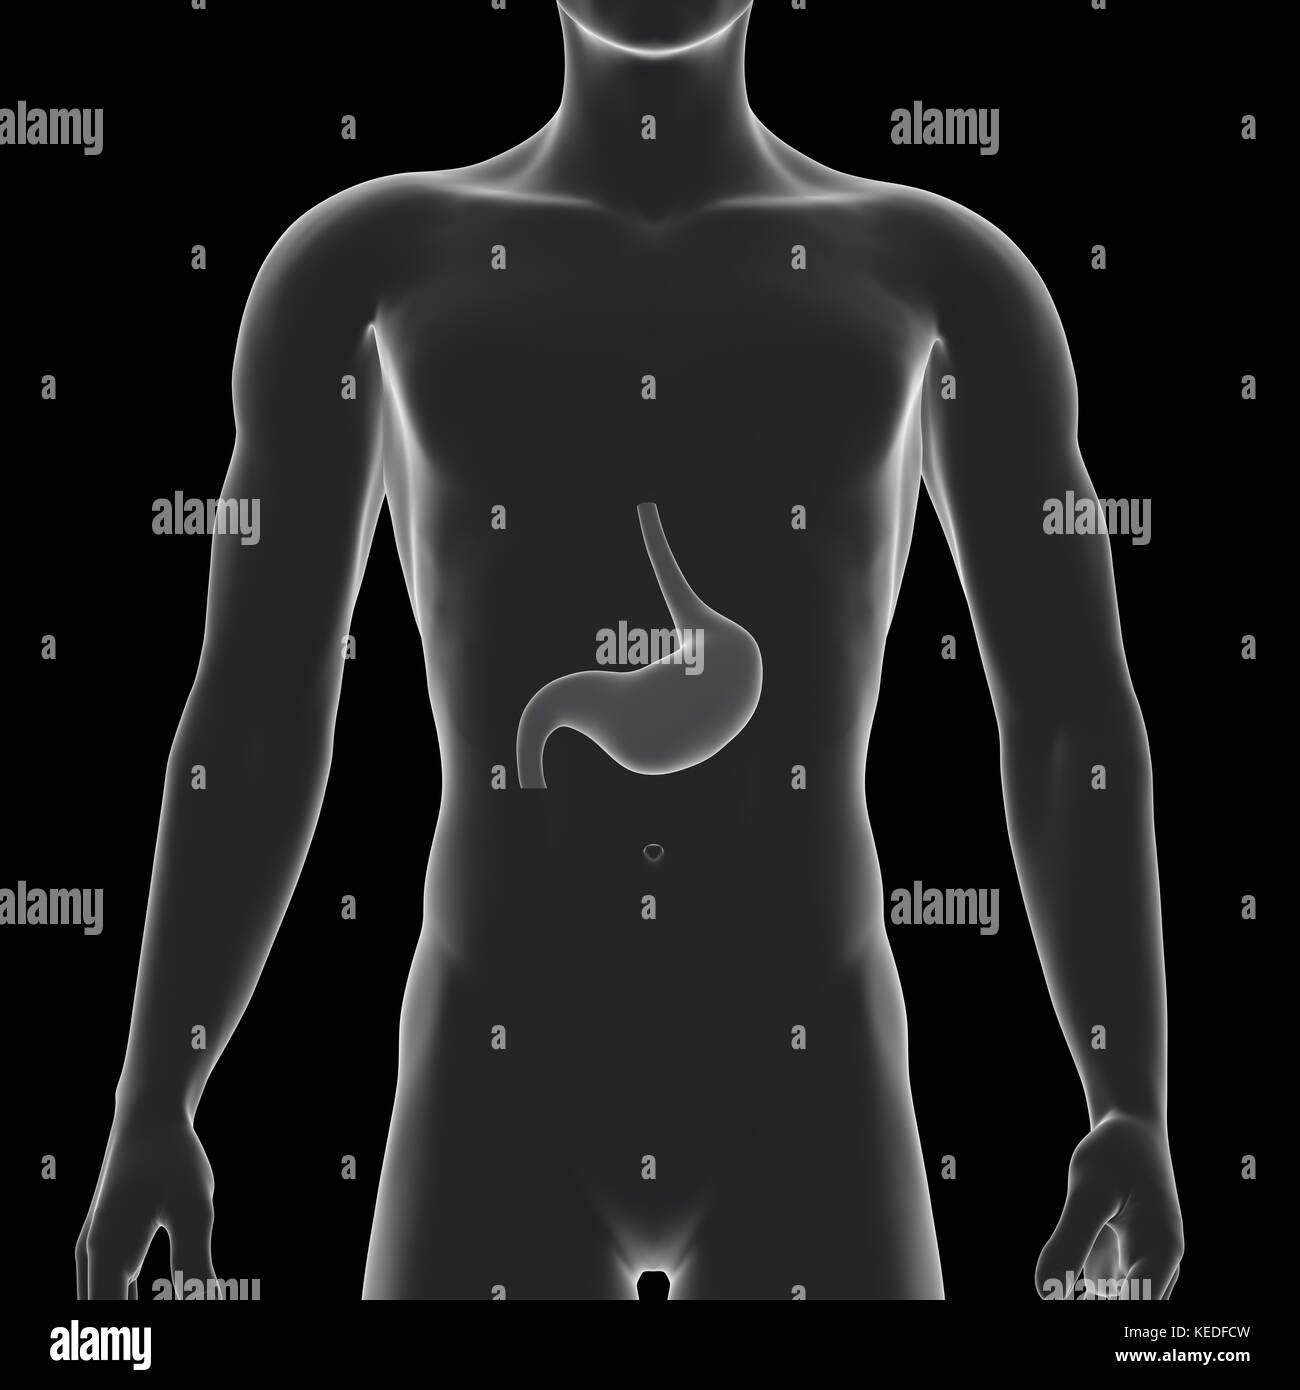

Stomach, Internal Organ, Human Body Stock Photohttps://www.alamy.com/image-license-details/?v=1https://www.alamy.com/stock-image-stomach-internal-organ-human-body-163795989.html

Stomach, Internal Organ, Human Body Stock Photohttps://www.alamy.com/image-license-details/?v=1https://www.alamy.com/stock-image-stomach-internal-organ-human-body-163795989.htmlRFKEDFCN–Stomach, Internal Organ, Human Body

Stomach, Internal Organ, Human Body Stock Photohttps://www.alamy.com/image-license-details/?v=1https://www.alamy.com/stock-image-stomach-internal-organ-human-body-163795987.html

Stomach, Internal Organ, Human Body Stock Photohttps://www.alamy.com/image-license-details/?v=1https://www.alamy.com/stock-image-stomach-internal-organ-human-body-163795987.htmlRFKEDFCK–Stomach, Internal Organ, Human Body

Human healthy stomach inside man sikhouette. Internal digestion organ. Low poly connected dots gray white triangle future technology design background vector medicine illustration Stock Vectorhttps://www.alamy.com/image-license-details/?v=1https://www.alamy.com/stock-image-human-healthy-stomach-inside-man-sikhouette-internal-digestion-organ-162004085.html

Human healthy stomach inside man sikhouette. Internal digestion organ. Low poly connected dots gray white triangle future technology design background vector medicine illustration Stock Vectorhttps://www.alamy.com/image-license-details/?v=1https://www.alamy.com/stock-image-human-healthy-stomach-inside-man-sikhouette-internal-digestion-organ-162004085.htmlRFKBFWT5–Human healthy stomach inside man sikhouette. Internal digestion organ. Low poly connected dots gray white triangle future technology design background vector medicine illustration